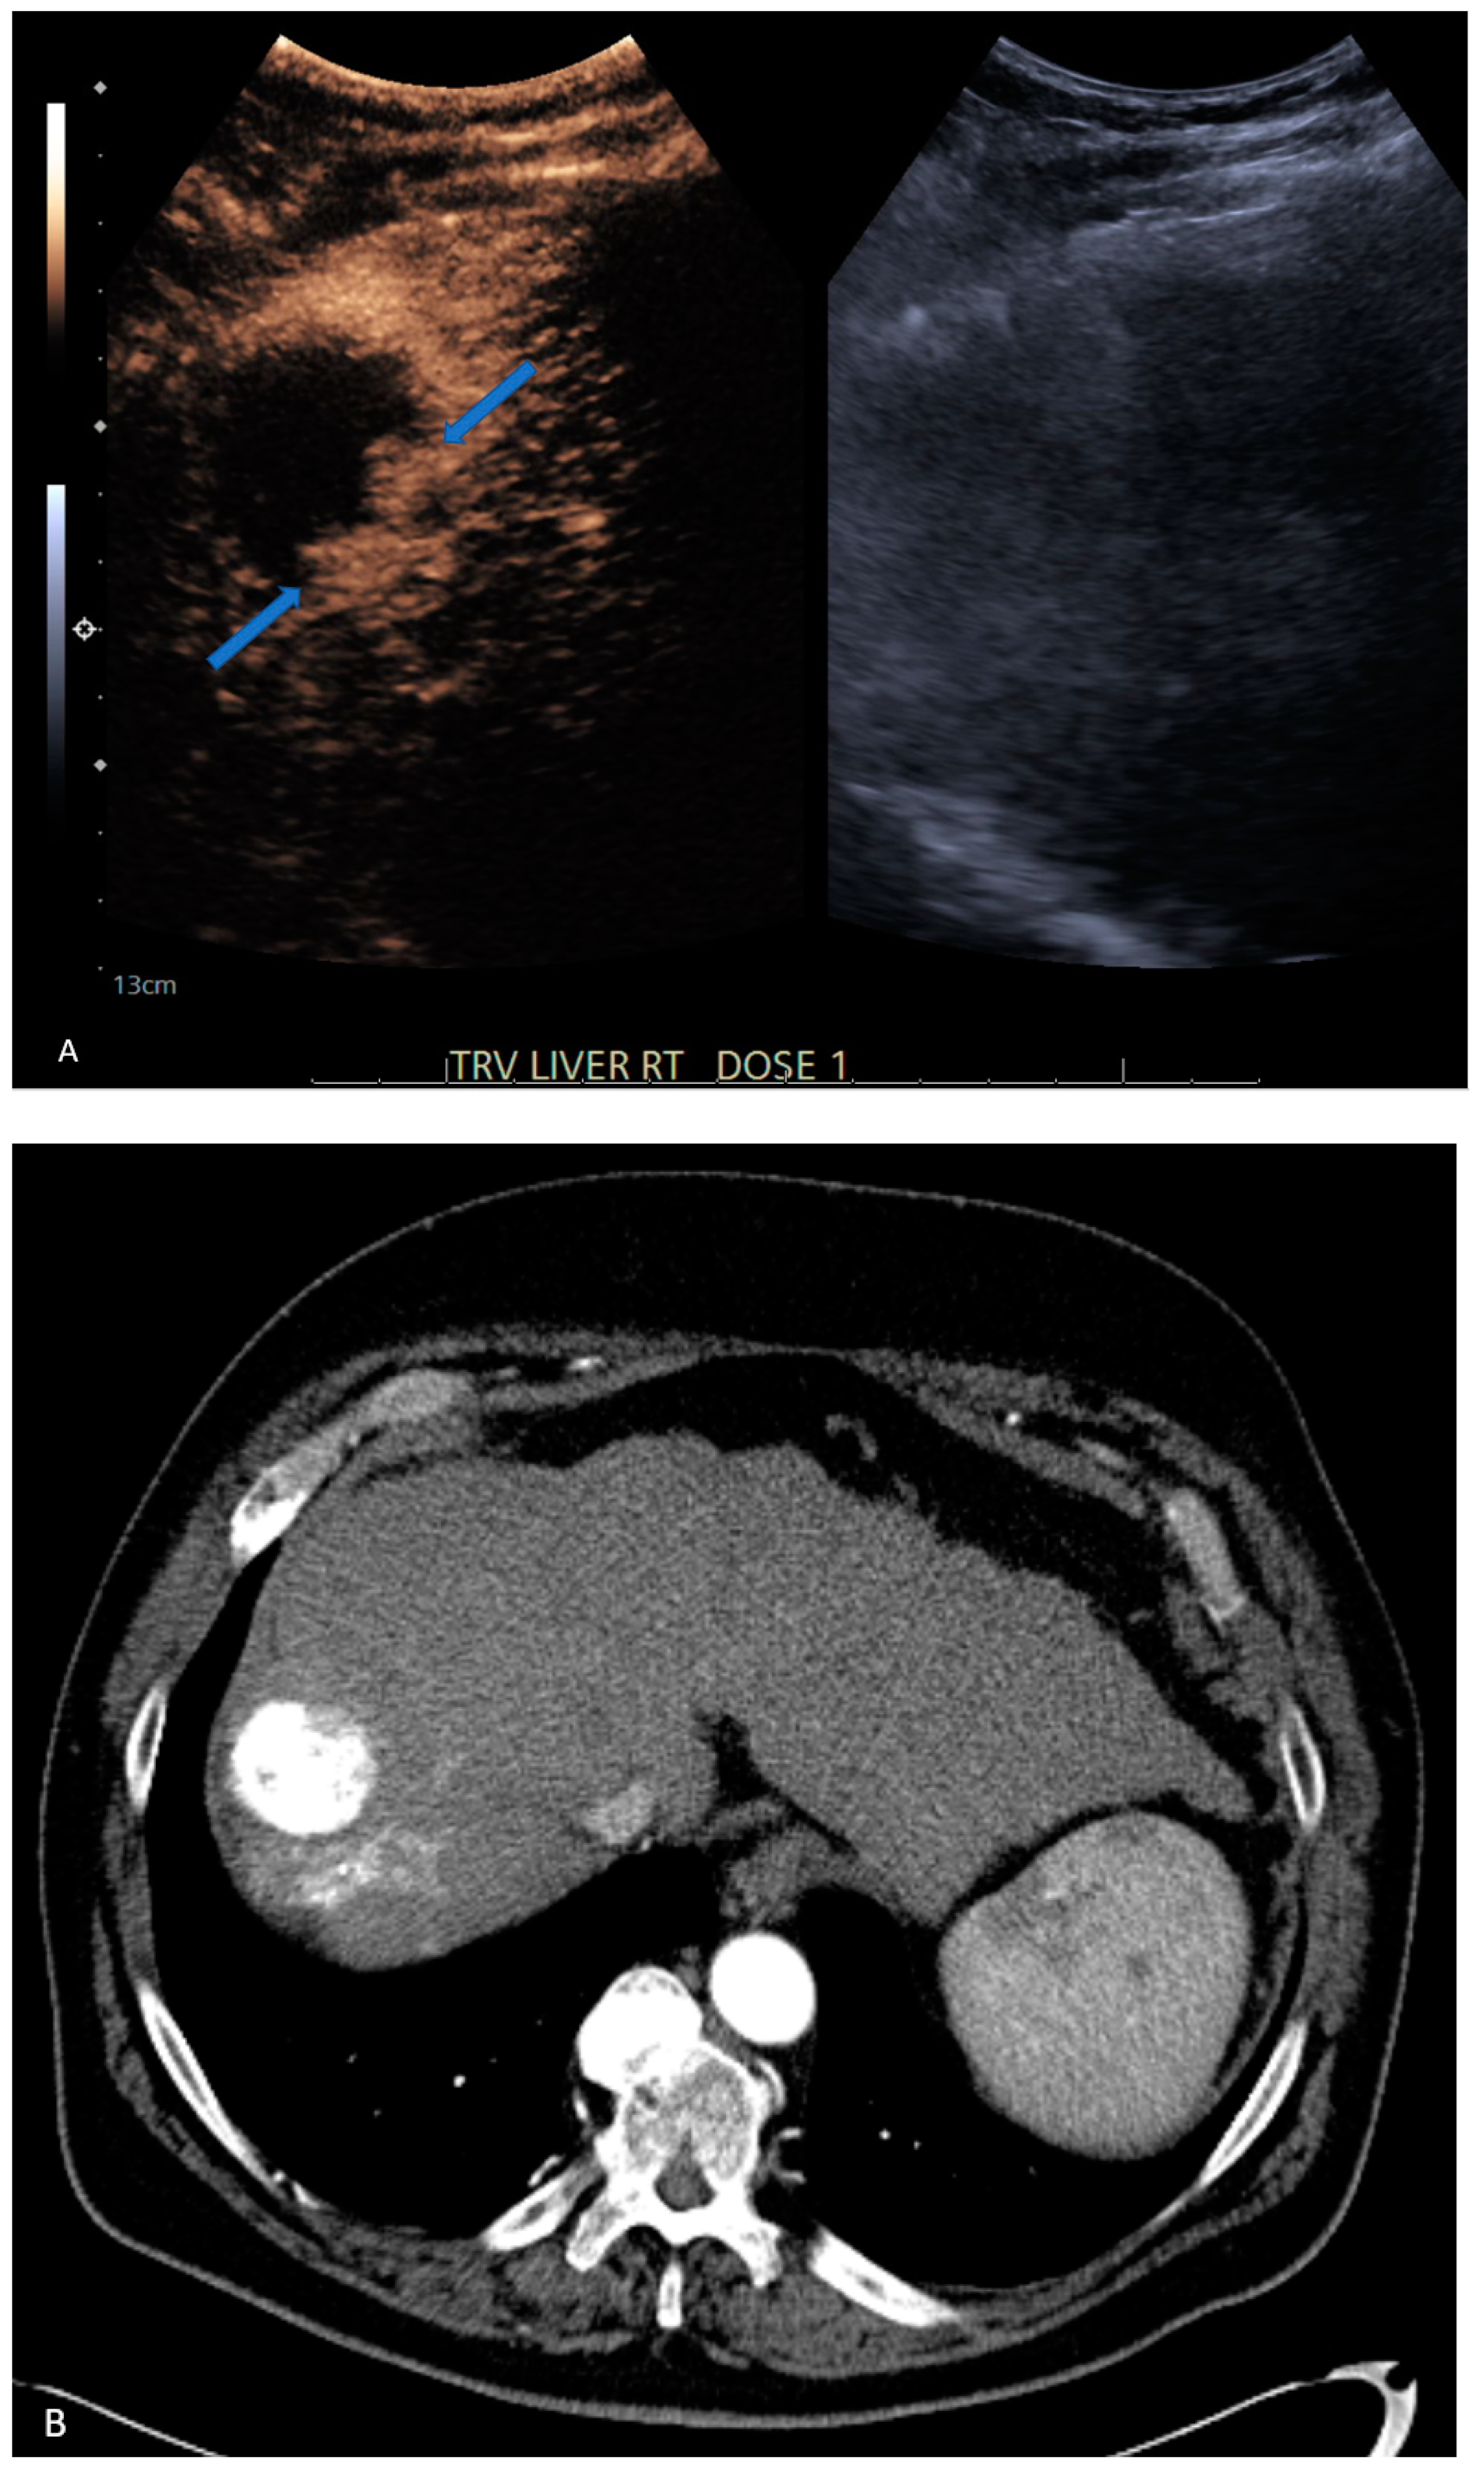

| 7 | CEUS | Target | LR-treated | CT called residual tumor, follow-up CT showed the area was perfusional, not disease (Figure 3) |